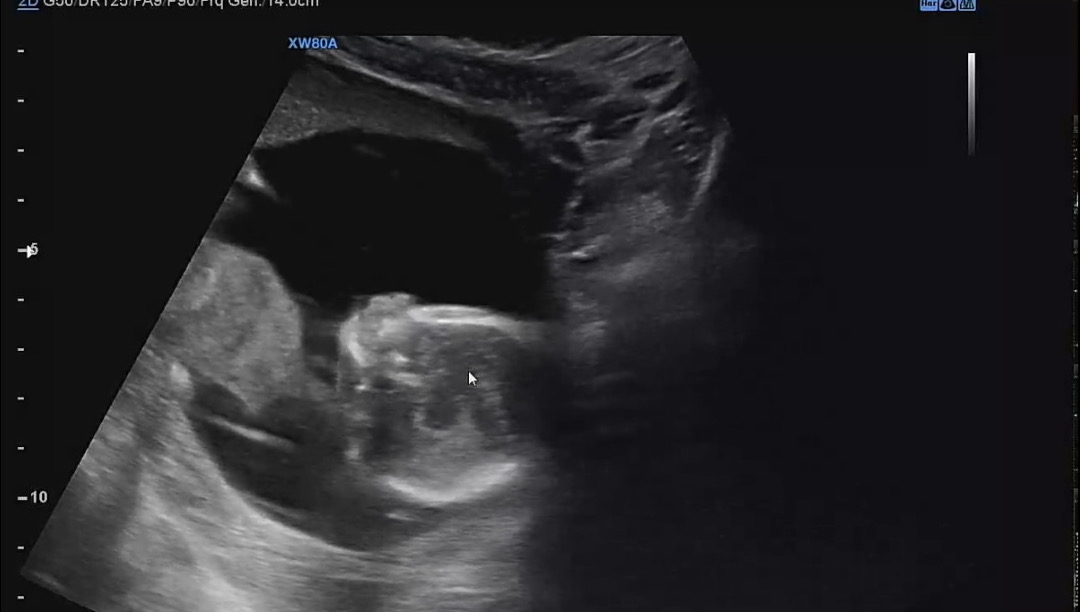

15주 1일👶🏻

어제 오랜만에 병원 다녀왔어요 💕 니프티 검사로 지난주에 성별 알았지만 오늘 초음파로 다시 한번 확인이 되었네요🩵 이리저리 꼼지락 꼼지락 움직여서 구석구석 보고 왔답니당 👶🏻🩵